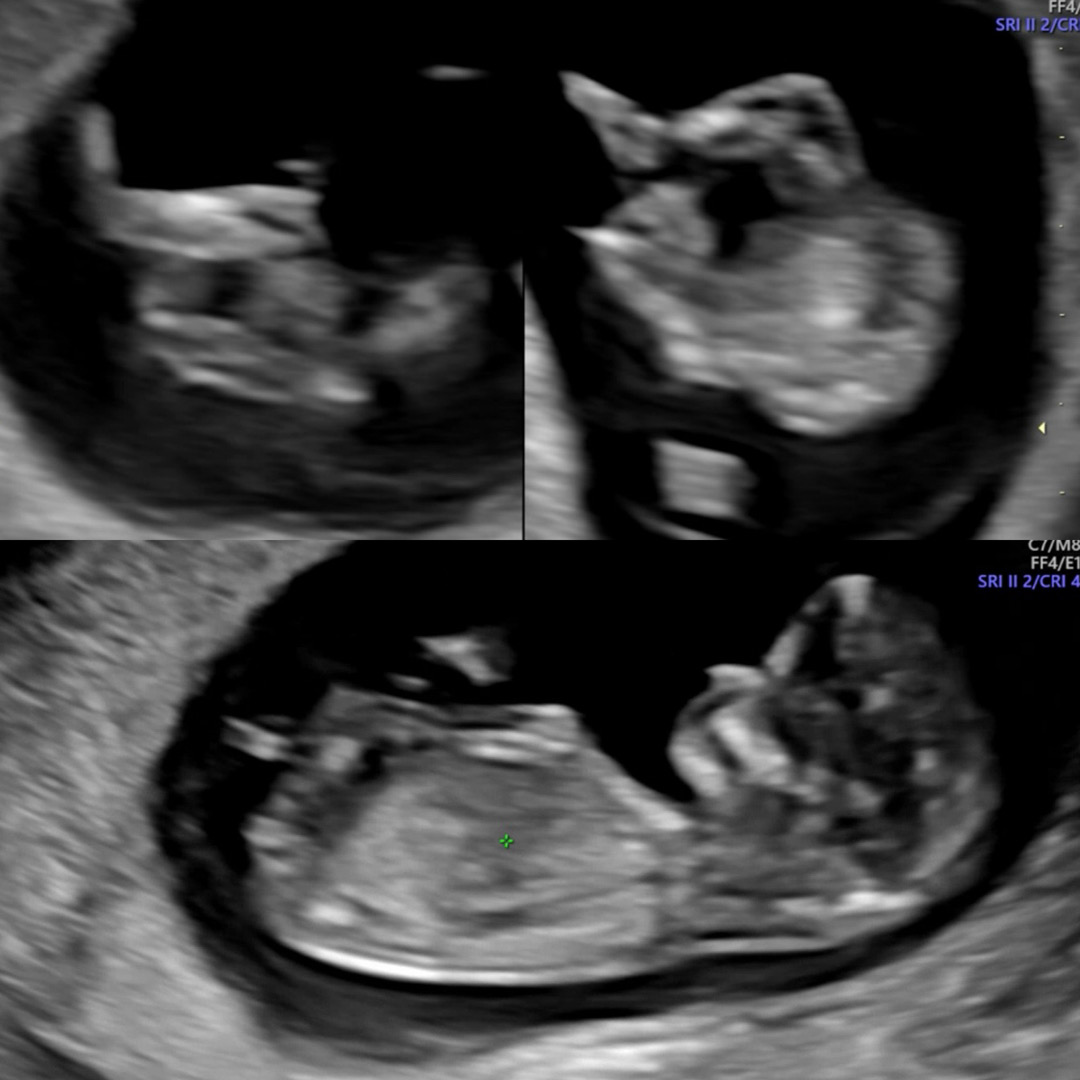

11주 5일차인가 찍엇음다 대충 찍어봐주실뿐!!!!!!!!! (위에 다리 !! 밑에 몸!!!)

딸같은데욤

입맛은상관없드라구요 근데 딸같아요

늦엇지만 딸이 맞앗어요 !!! 다들 어뜨케 아셧는지 !!!